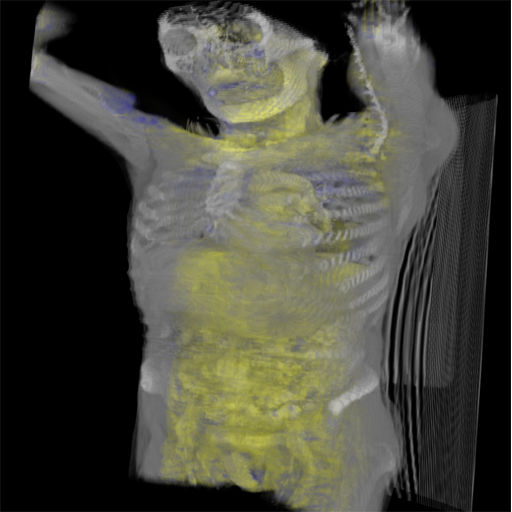

Figure 41.1 depicts a human torso and part of a skull (OpacityMapRenderStyle) blended with a blue/yellow tone-mapped volume of the internal organs. The image shows how BlendedVolumeStyle allows two different volumes to be combined, each with its own render style.

Figure 41.1 — Torso in BlendedVolumeStyle